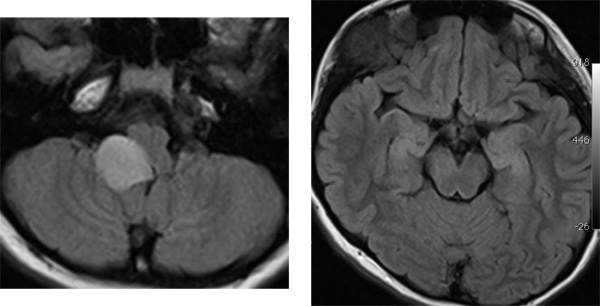

14歳の時のMRI

延髄の病変は4年間大きくなり続けていますが我慢して経過観察をします,このような時に,組織を採ってみないと診断がつかないと言われて,生検手術などをされてしまうことがあります(>_<)

逆に中脳(左の写真)の病変は消失しました